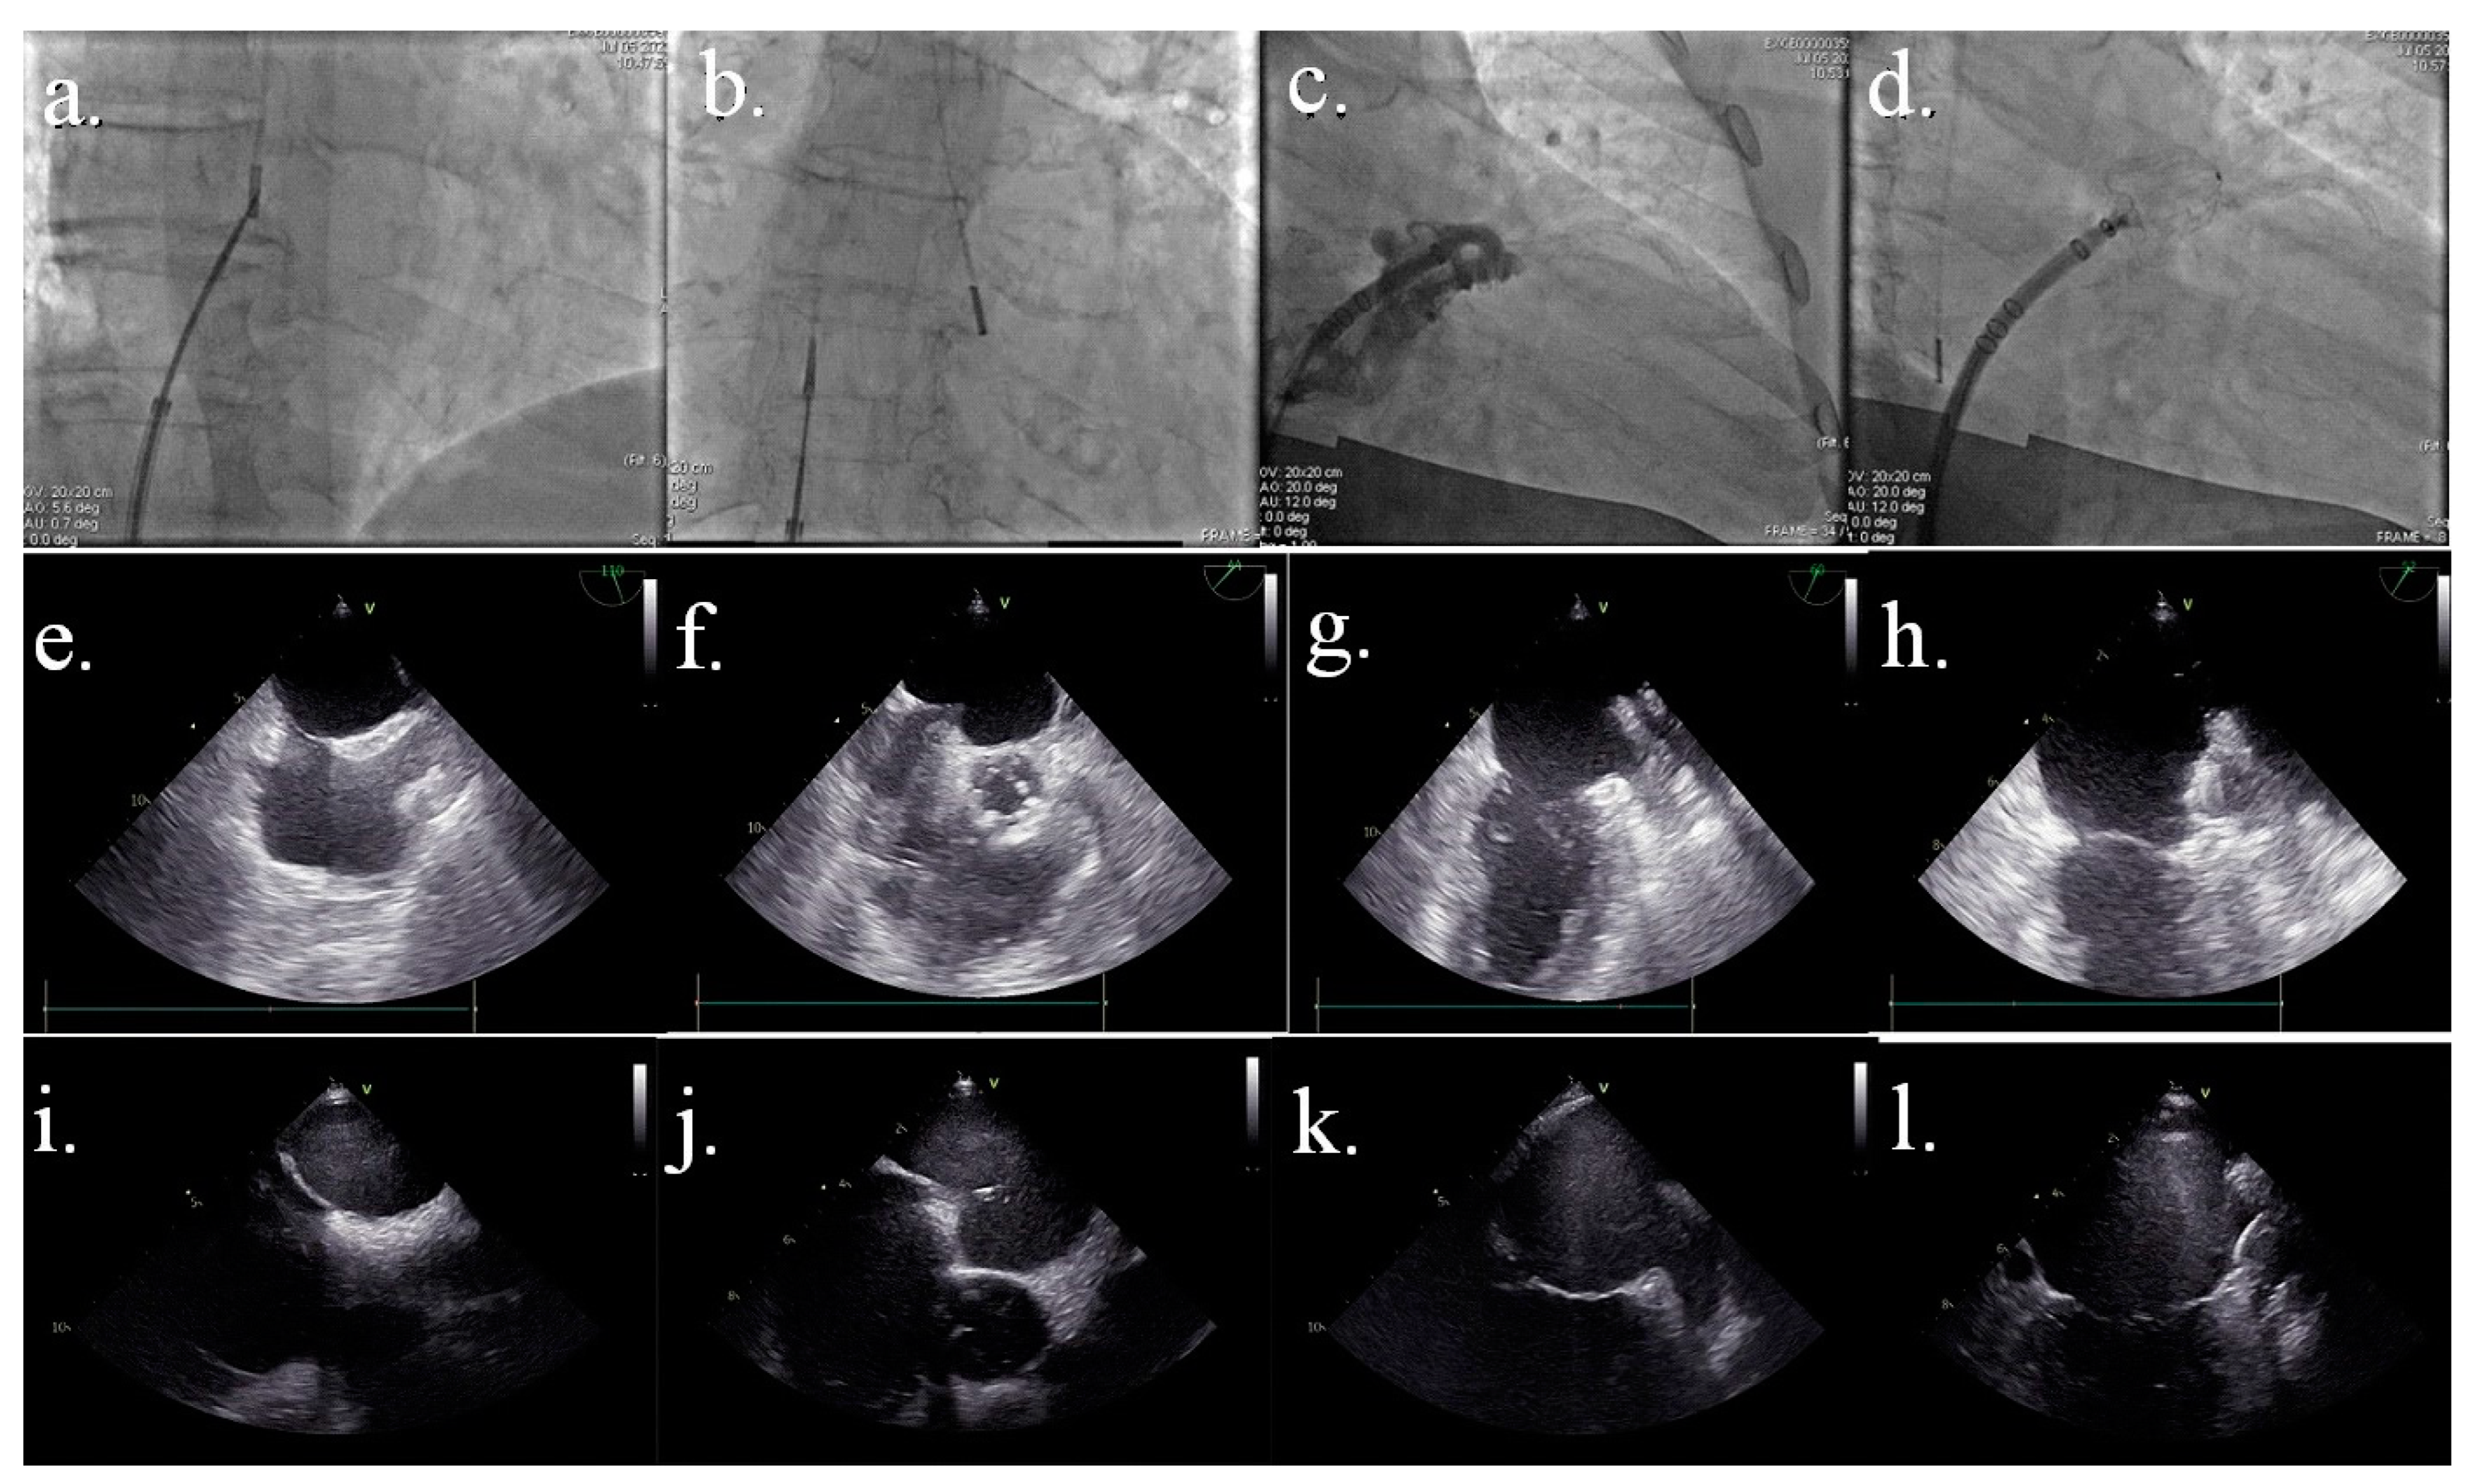

2. Procedural Steps

3. Fluoroscopy

4. TEE

5. Intracardiac Echography (ICE)